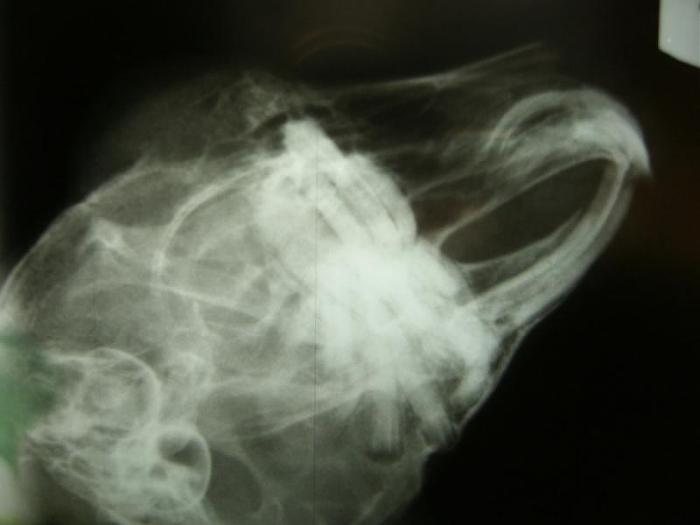

Es gibt ja schon leckere Sachen hier, aber ich sitze davor und kann sie nicht kauen weil es nicht geht

Und sie hat nicht nur mich voll unvorteilhaft geknipst, neeeeeeee sie tut Euch auch noch meinen Kopf von innen zeigen. Ganz schön krumm und schief bin ichNur mein Bauch und mein Herz sieht toll aus